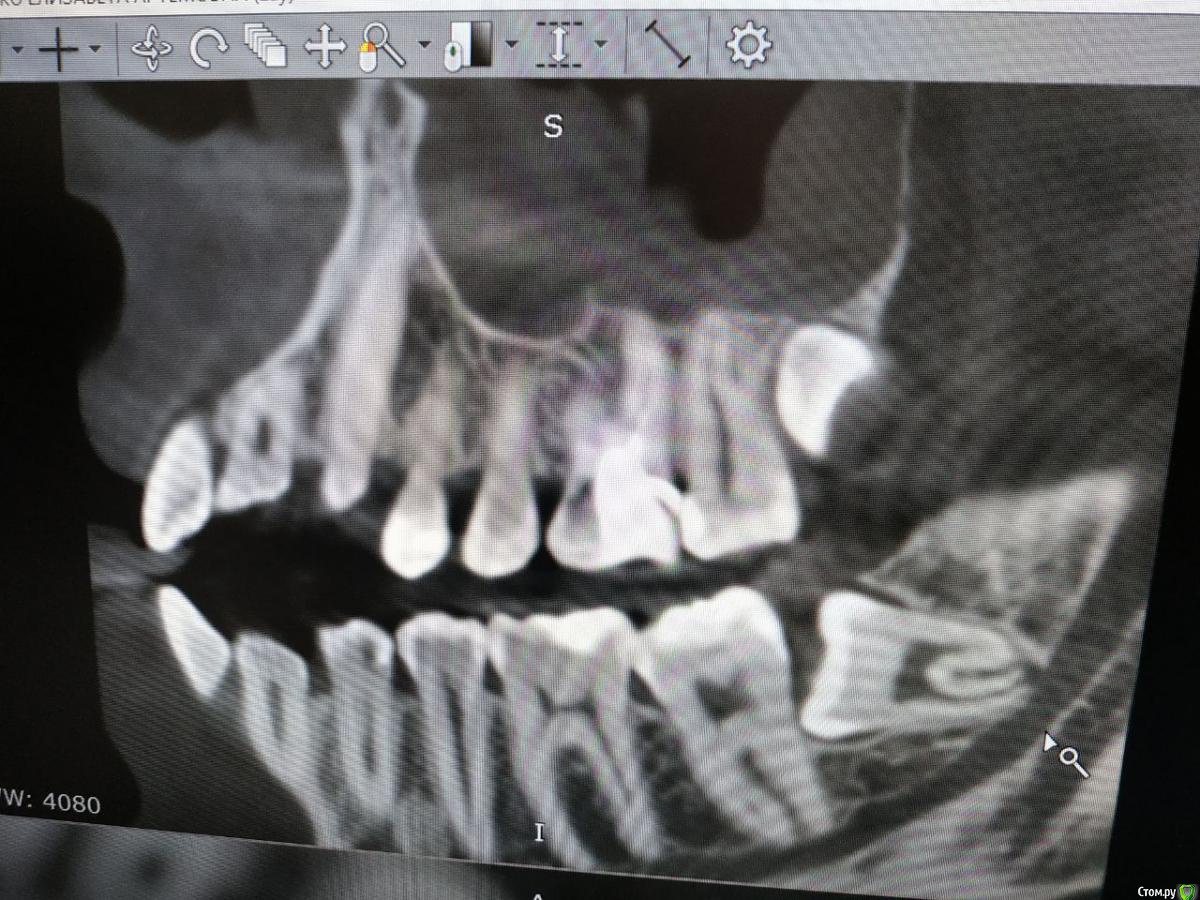

Liza544 Опубликовано 3 февраля, 2020 Поделиться Опубликовано 3 февраля, 2020 Добрый день.Помогите, пожалуйста, разобраться с причиной боли.Началось все приблизительно в начале октября (3 мес назад). Обратилась к стоматологу на проф осмотр, в ходе которого у меня обнаружили пульпит в 26-м зубе. В результате - удалили 3 нерва, но, со временем я обнаружила, что боль не прошла. Обходила несколько клиник. В ходе этого сделала пломбу на соседнем 25-м зубе. Совсем недавно удалила в том же 26-м зубе 4-й "маленький" нерв, так как сначала его не удалили, потому что не заметили (удаляла в клинике без микроскопа).В итоге, боль осталась прежней. Боль в области состыковки 26-го и 25-го зубов (при прикусывании на эту область). Наиболее логичными и вероятными предположениями, как по мне, являются: 1) 28-й зуб (зуб мудрости) , который у меня не удален - давит на соседние зубы и вызывает данную боль. Но, почему тогда, не болит 27-й? хотя, когда между 27 и 26-м провожу ниткой - есть кровь. 2) Воспалена десна. Один из стоматологов выразил данное предположение и в принципе оно может иметь место, так как когда вожу ниткой между 26-м и 25-м - болит десна. Но почему тогда так же болит и при надкусывании? К тому же, если в 26-м нету нервов, так как их удалили, как он вообще может болеть? Непонятно... Прилагаю снимки 25, 26, 27 и зуба мудрости.Буду очень признательна за хоть какие-нибудь предположения и комментарии. Спасибо. Ссылка на комментарий

Liza544 Опубликовано 4 февраля, 2020 Автор Поделиться Опубликовано 4 февраля, 2020 Вот еще пару снимков которые у меня есть. ПРошу заметить, что последние 4 снимка (файлы 7-10), которые я тут прикрепила - до пломбы на 25-м зубе и до залеченного 4-го канала в 26-м зубе. Подскажите пожалуйста, может ли быть зуб недостаточно залечен, хотя на КТ ничего подозрительного не видно? Ссылка на комментарий